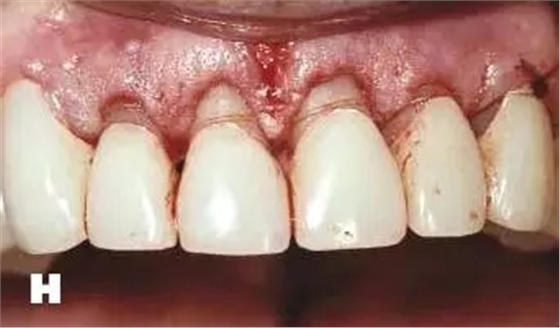

牙周炎發(fā)展到一定階段時(shí),僅采用基礎(chǔ)治療難以取得較好療效,必須通過適時(shí)而合宜的手術(shù)治療挽救患牙,才能保持牙周組織健康,延長患牙在口腔內(nèi)的壽命,維持牙列的完整性,促進(jìn)全身健康。其手段包括齦下刮治、根面平整、牙周翻瓣術(shù)、牙齦切除術(shù)、牙周夾板固定術(shù)等。